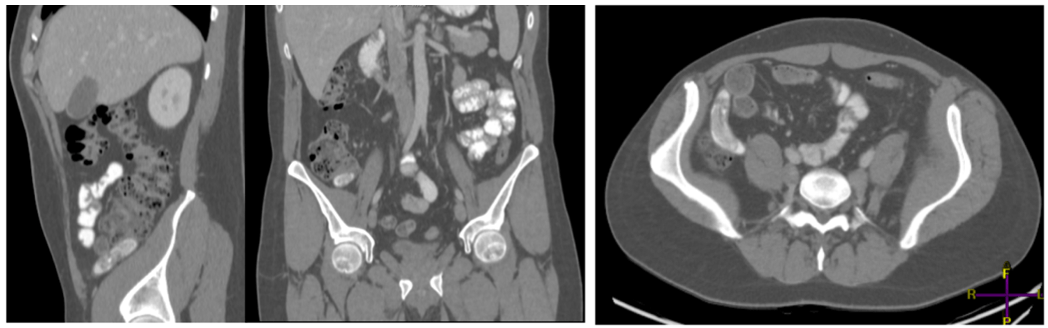

CT with intravenous contrast: Confirmed dilatation of the vermiform appendix (Red arrow), showing heterogeneous hyperdense content with layering and measuring 56 x 16 mm. It contains hyperdense material and calcifications (appendicoliths), with no evidence of local complication. This suggests an appendiceal tumor, likely mucinous in origin.

No free fluid or peritoneal implants are detected. Mild mural thickening (3 mm) of the terminal ileum is observed, with no associated local inflammatory changes to indicate active inflammation (Fig 2).